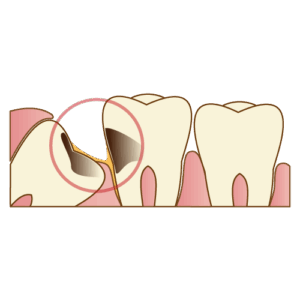

(1) ドライソケット

症状: 抜歯後3〜4日目頃から、抜いた穴の奥からズキズキとした強い痛みが始まり、耳の奥や側頭部などに痛みが放散するのが特徴です。

-

原因: 前述の「血餅(かさぶた)」が、過度なうがいなどによって剥がれてしまい、抜歯窩の骨が露出した状態(骨の表在性骨炎)です。

-

発生率データ: 国内のある調査では、**下の親知らずの抜歯1146症例中62例(5.41%)**にドライソケットが発生したと報告されています。

また、別の報告では、喫煙者は非喫煙者(発生率4%)に比べ、発生率が12%と約3倍高かったというデータもあります。

抜歯前後の禁煙は非常に重要です。